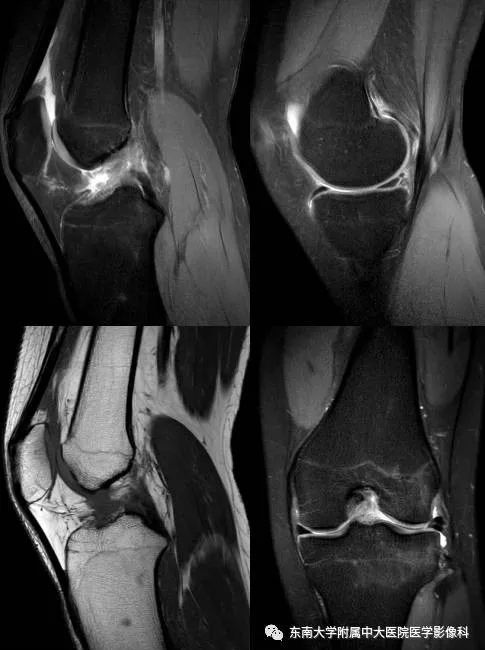

女,16岁,因“外伤致左膝疼痛伴活动受限2月余”入院。

MR

病例结果:前交叉韧带损伤